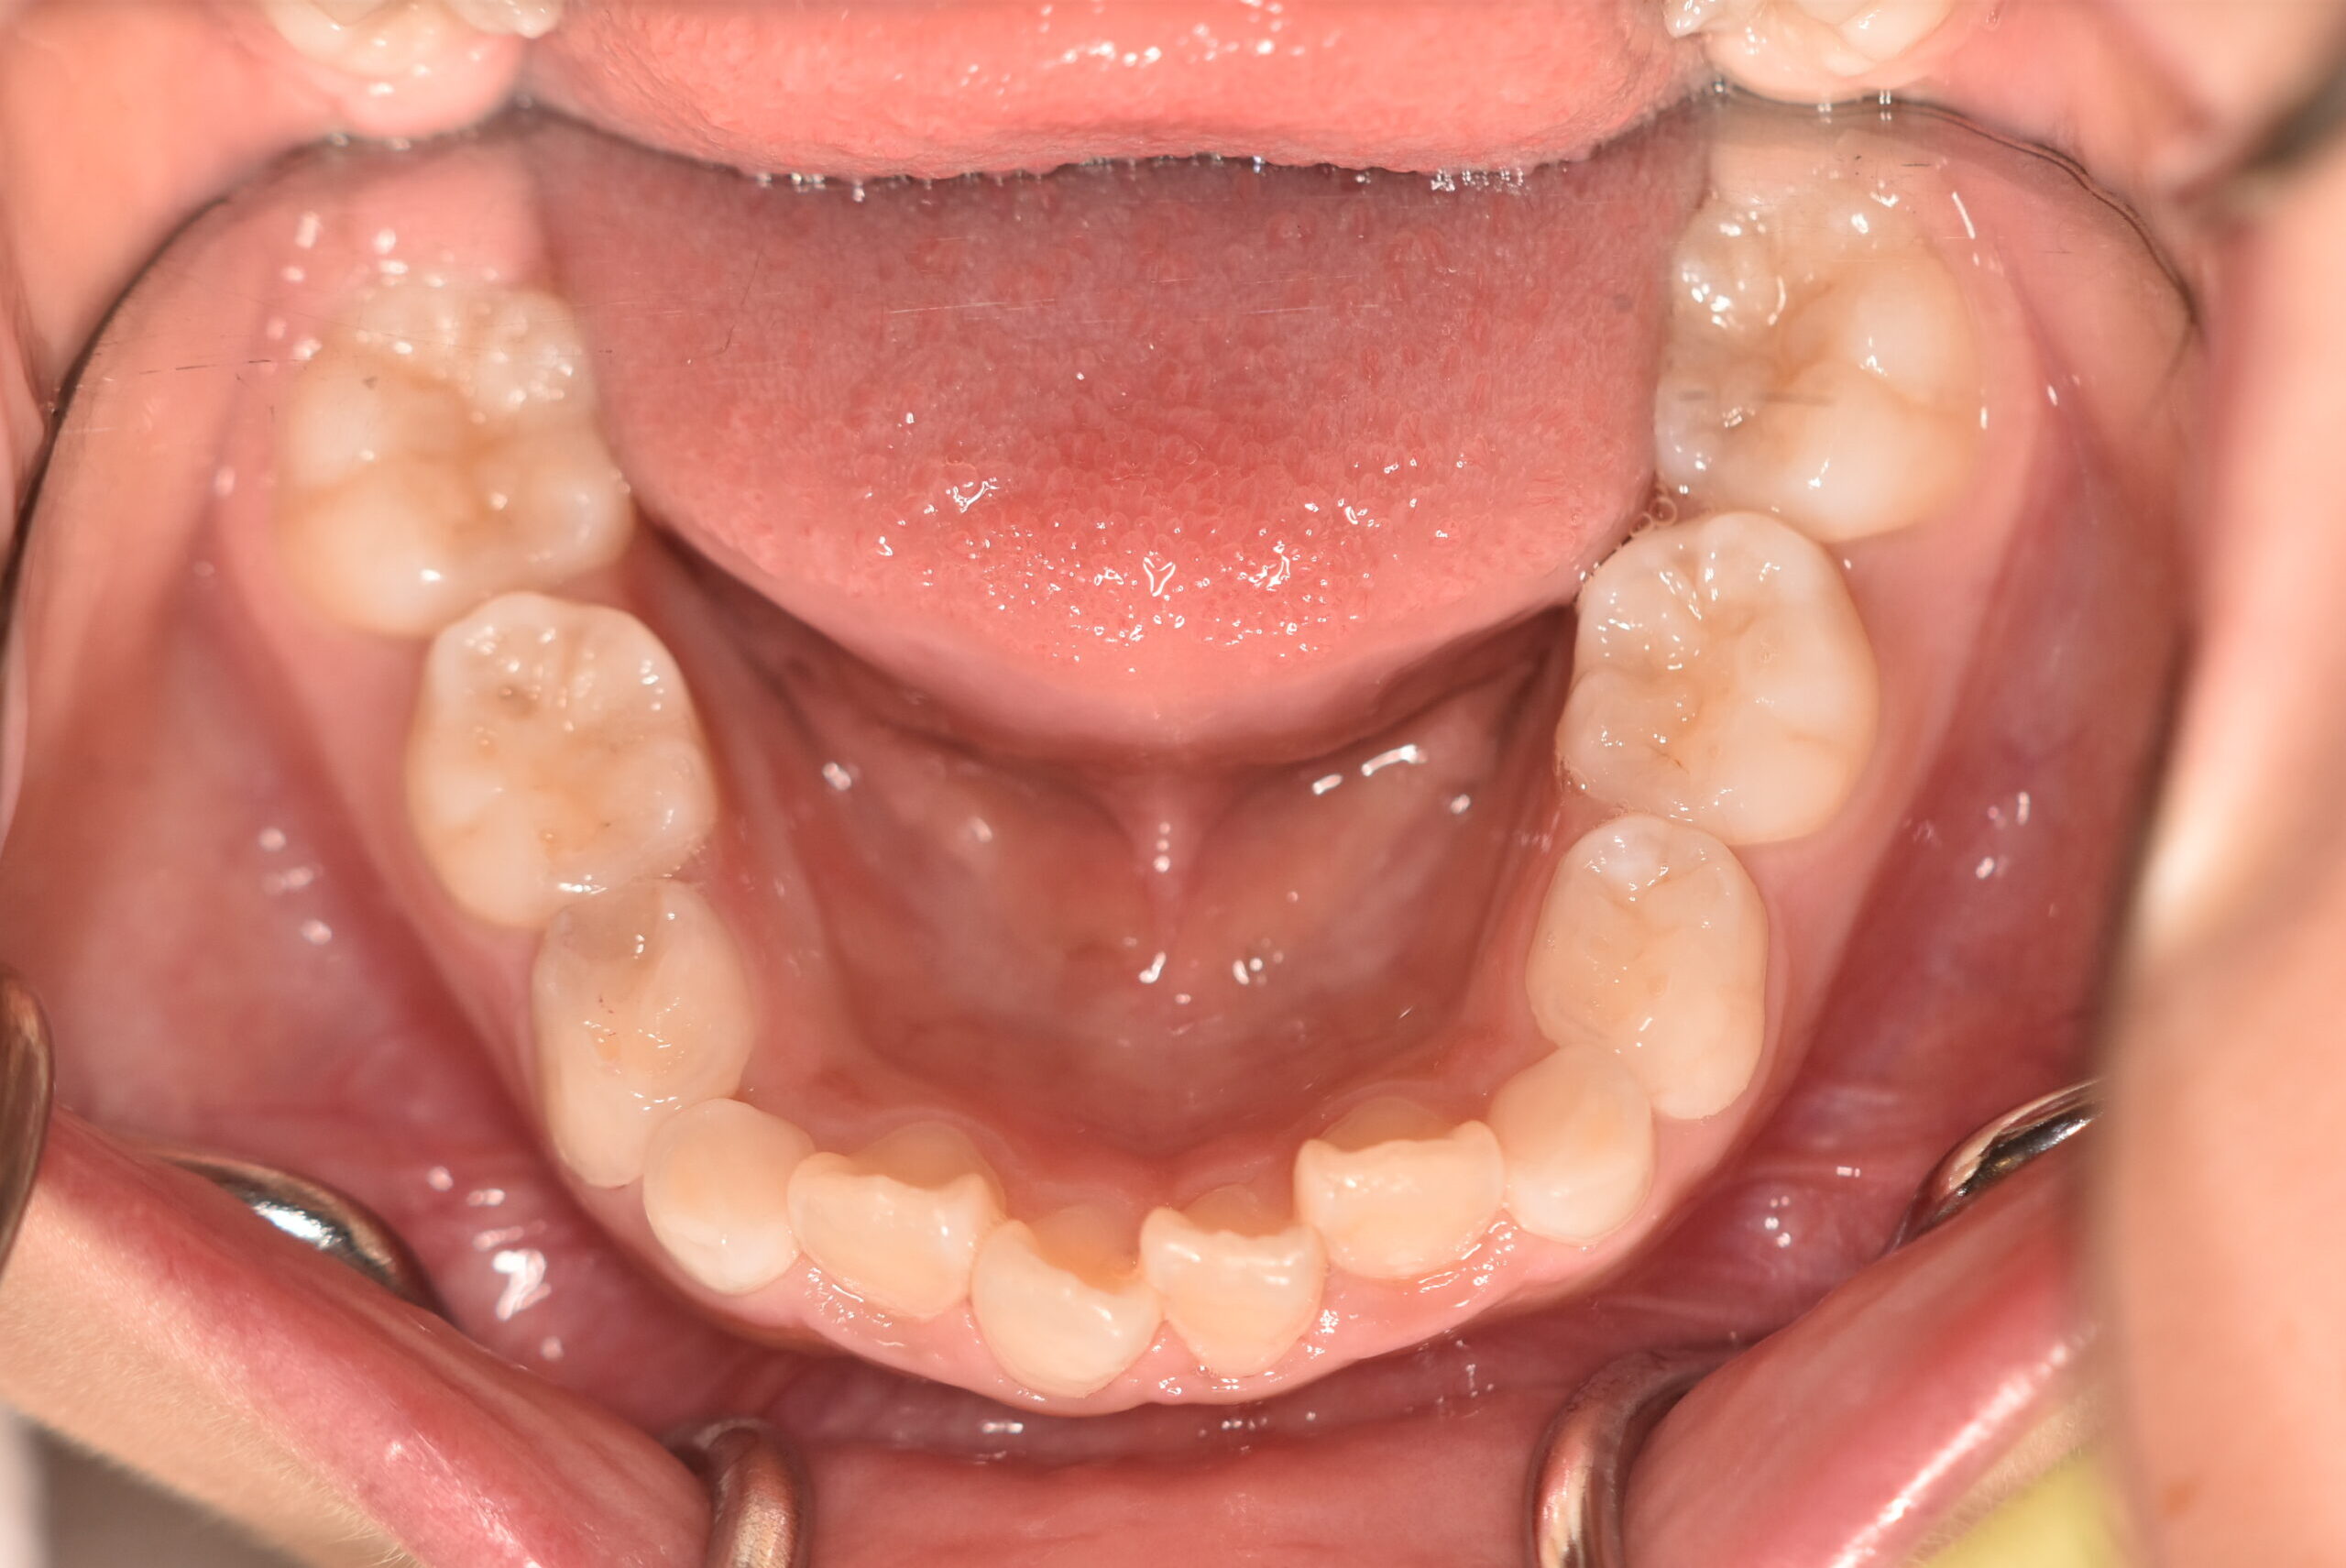

| 治療内容の詳細 | 初診時7歳の女児で、歯のがたつきを気にされ来院されました。 検査の結果、前歯部叢生を伴うアングルⅡ級不正咬合と診断しました。 治療としてはマウスピース矯正(インビザラインファースト)で配列を行い、上下顎の側方拡大と萌出スペースを確保しました。 治療期間は、1年でした。 今後、側方歯生え変わりまで経過観察を行います。 |